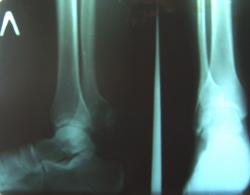

Пациент 19 лет. Призван в декабре 2008 года. В госпиталь поступил в марте 2009 года. У меня вопрос. Не что это? С этим все в прорядке. Пациент прооперирован, выздоравливает. Вопрос в том, как это попало в армию. Не нужно проводить рентгенологического исследования. Все было видно не вооруженным взглядом и очень мешало ношению армейской обуви. Достаточно было пациента разуть при призывной комиссии.

Да уже не комментируется, как осматривали этих подростков в школах "с целью - профосмотры" наши коллеги их ЛПУ. Представленные снимки не совсем четкие, но, по всей видимости, дело имеем с хондромой или другим новообразованием?